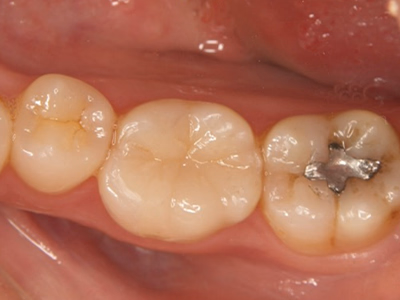

奥歯の詰め物(コンポジットレジン)

治療前後写真

治療前

治療後

28歳・女性

銀歯が取れて少ししみる

マイクロスコープ下でカリエス除去

コンポジットレジン充填(溝に着色レジンを用いて形態・色調再現)

治療期間

1日(約60分)

35,000円

補綴の再治療は歯髄損傷リスクが高まる

残存歯質が少ない場合は歯の破折リスク

医院コメント

小範囲の欠損に対して1回法で審美的に修復。

清掃性と見た目を両立。